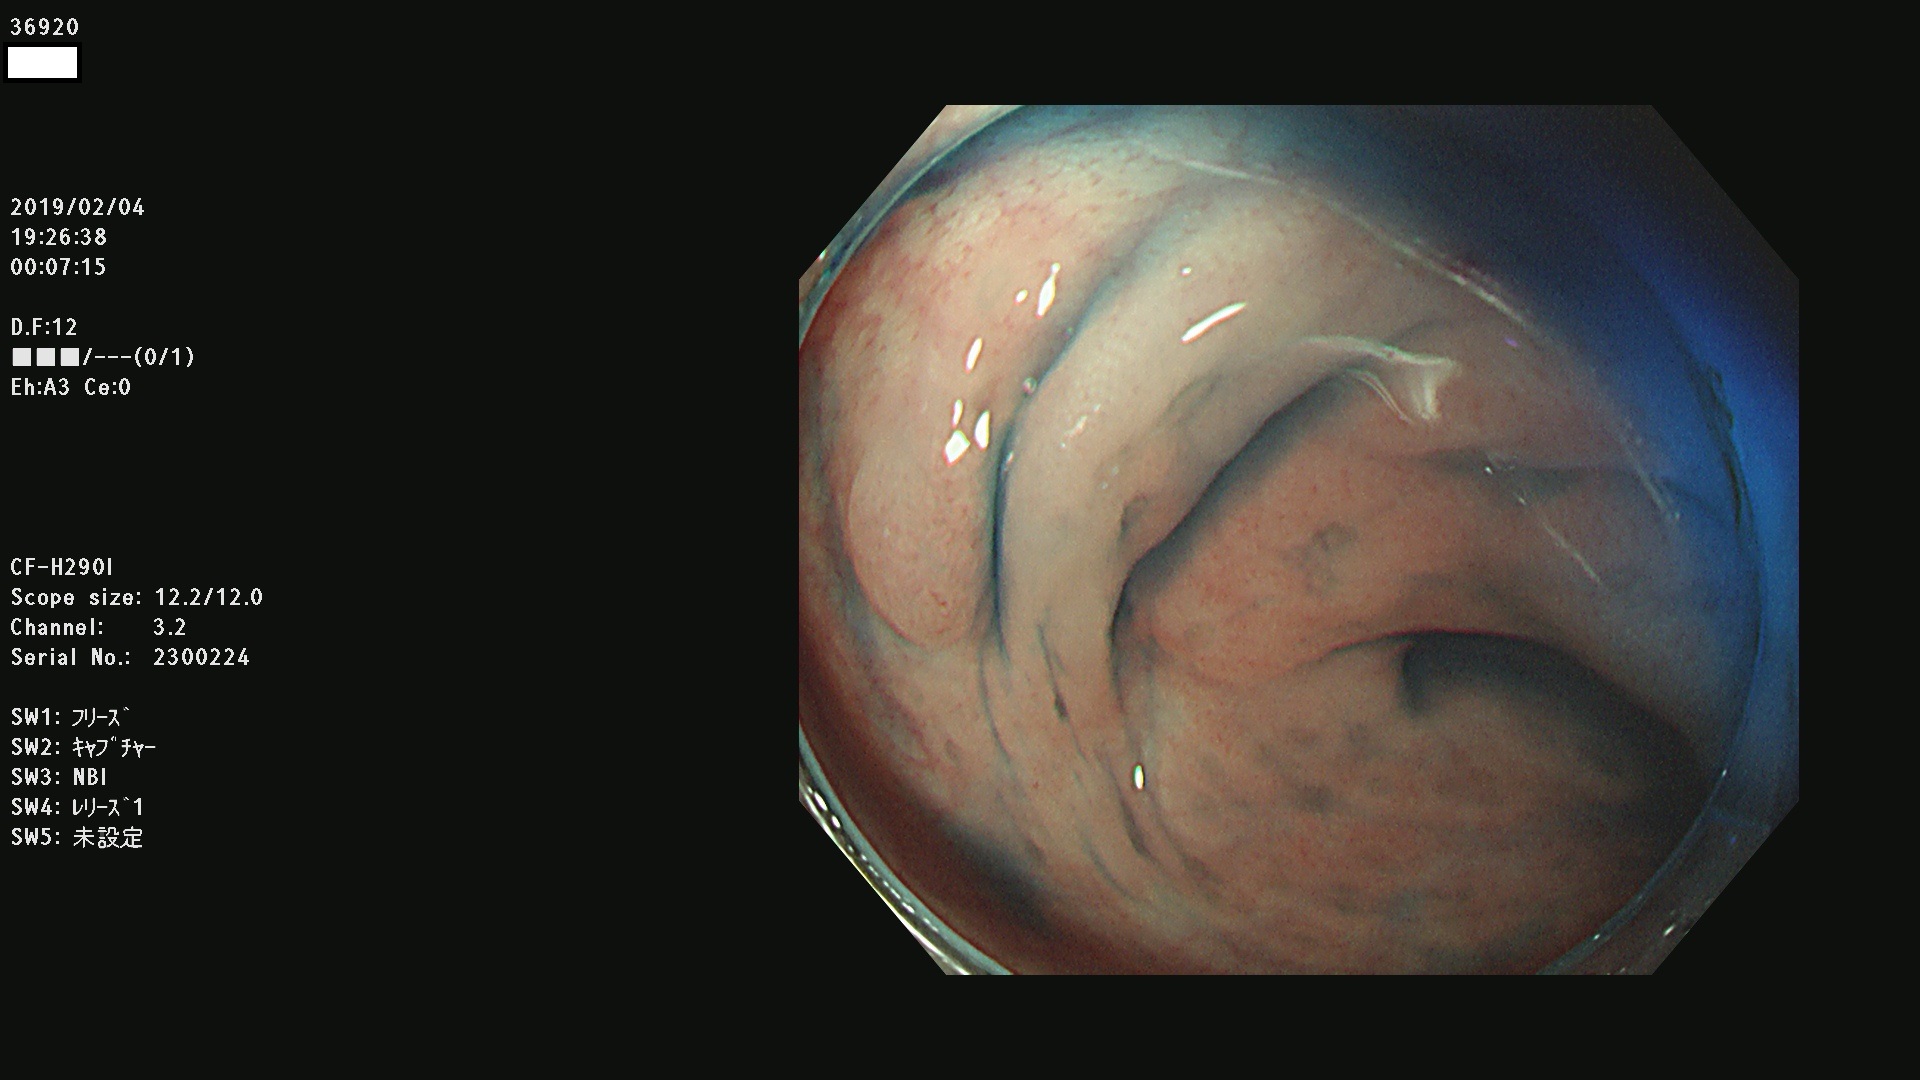

腺腫発見率 67 % (カルテ番号 36900〜36999の100名の方の検査結果で集計)大腸癌検診最新情報

以下のカルテ番号の方に腺腫(Adenoma,Group3〜5)が見つかりました(集計法)

36900 36901 36903 36904 36905 36908 36909 36910 36911 36913 36914 36915 36916 36917 36918 36919 36920 36923 36924 36925 36927 36928 36930 36931(SSAPのみ) 36933 36935 36936 36937 36941 36943 36944 36945 36946 36949 36951 36953 36954 36955 36957 36963 36965 36966 36967 36968 36969 36970 36974 36975 36976 36977 36978 36979 36980 36981 36983 36984 36986 36987 36988 36989 36990 36991 36993 36994 36996 36998 36999

発見困難で危険性の高い平坦型病変(上記100名より抽出) ![]()